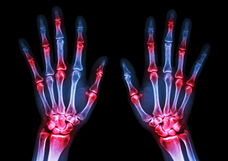

Las enfermedades reumáticas, como la artritis reumatoide, la artritis psoriásica o la gota, pueden provocar inflamación de la membrana sinovial. Esta inflamación suele generar dolor, hinchazón y aumento de la temperatura en la articulación.